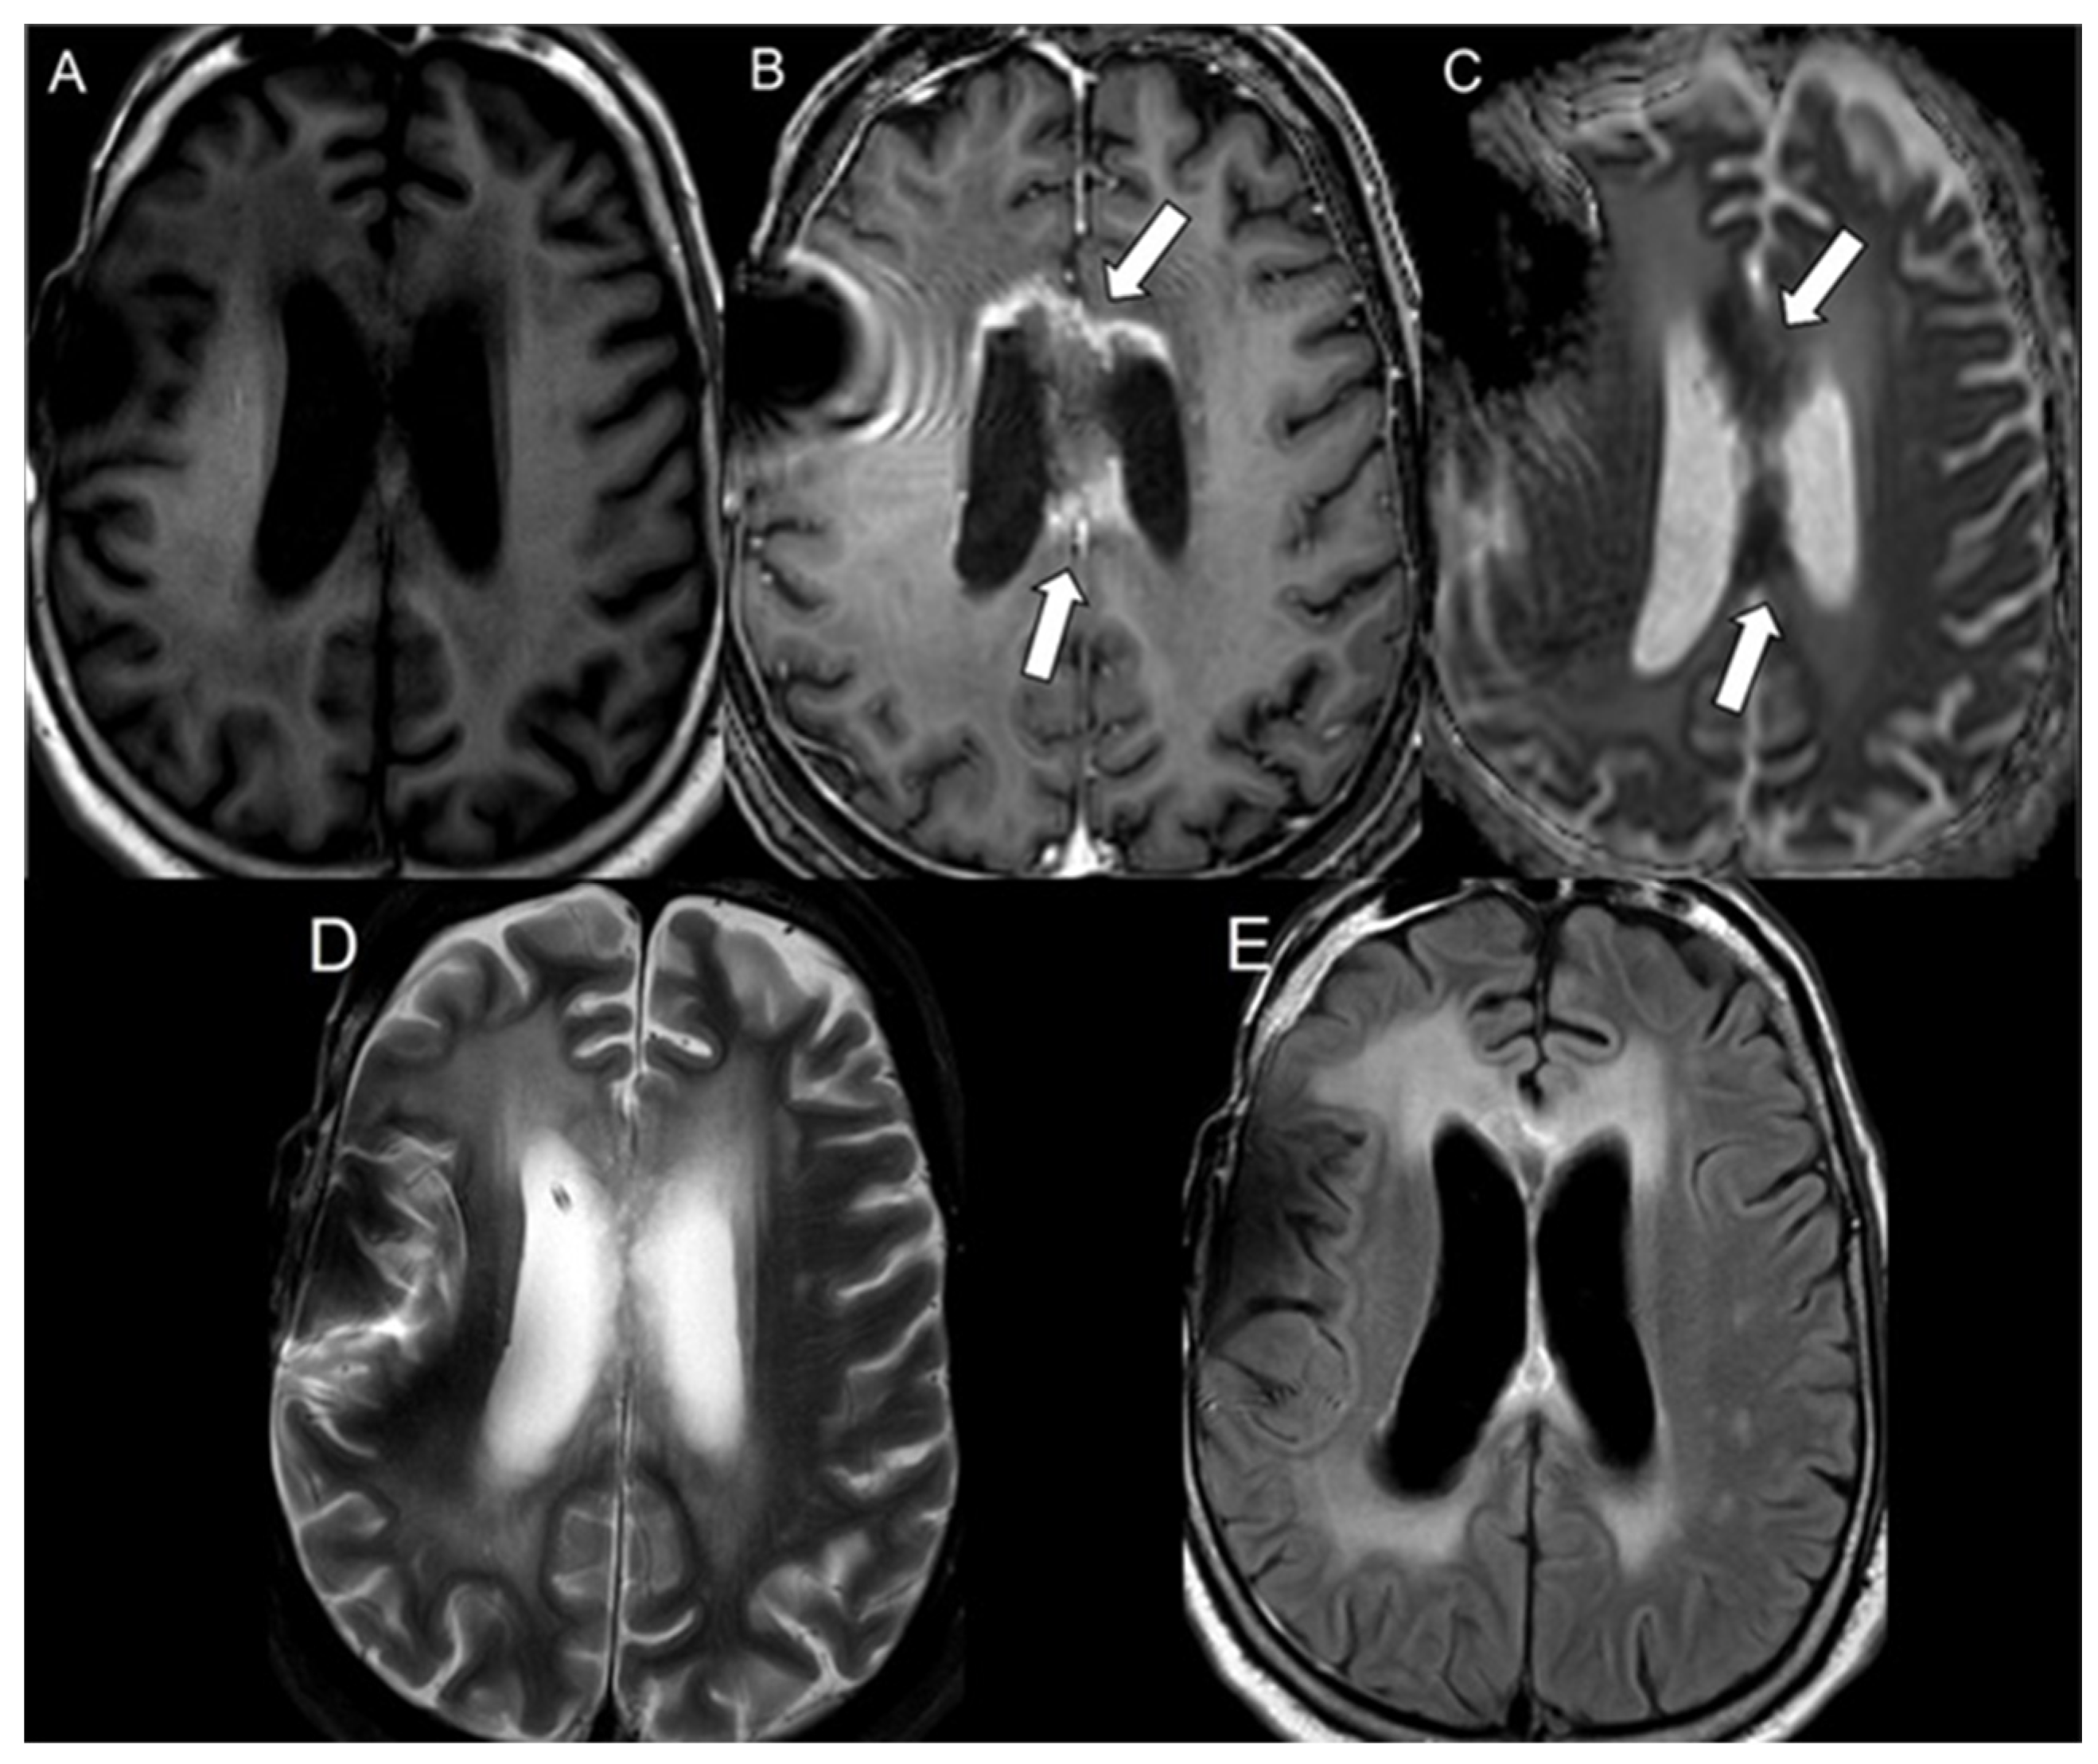

| Group | N | Lesion | Normal | p Value |

|---|---|---|---|---|

| Mean ± SD | Mean ± SD | |||

| Bevacizumab | 21 | 248.1 ± 67.2 | 647.2 ± 94.6 | <0.001 |

| Progressive glioblastoma | 49 | 752.8 ± 132.5 | 709.2 ± 63.5 | 0.08 |

| Radiation necrosis | 58 | 479.0 ± 105.2 | 723.3 ± 64.0 | <0.001 |